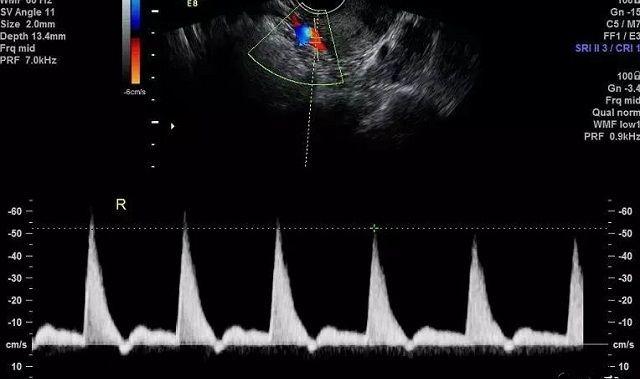

试管婴儿胚胎移植前,医生会安排宫腔镜、阴超等检查项目,其中准备内膜期间会多次复查内膜情况,尤其是子宫动脉血流,若有异常则本周期不会建议移植。

B超报告示例

医生常常采用超声检查测量子宫动脉血流动力学参数,来了解子宫动脉供血情况,这些参数包括搏动指数(PI)、阻力指数(RI)、收缩期峰值流速/舒张期流速(S/D)。

B超呈像示意图

二维阴道超声下子宫横切面扇形扫查,在子宫近宫底处探及约3-4mm无回声信号,加CDFI显示子宫动脉血流信号,在将频谱(PW)取样容积放置在子宫动脉血流处取样。

获取3-5个连续稳定,形态均匀一致的血流图。测量计算出子宫动脉收缩期流速、舒张期流速、血管阻力指数。